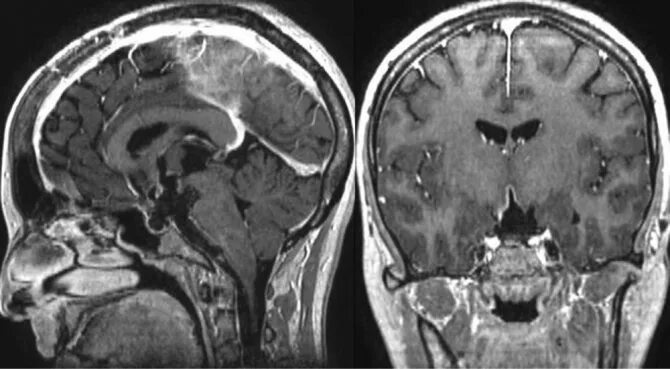

Умеренная дисфункция диэнцефальных структур мозга